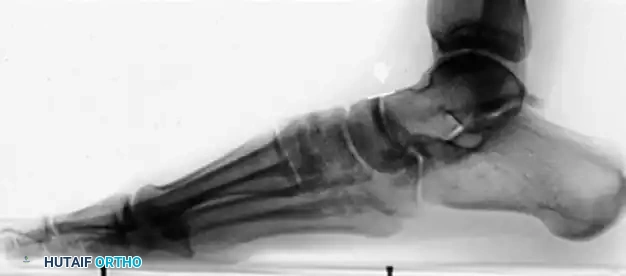

When the posterior tibial tendon (PTT) fails, the medial longitudinal arch collapses, leading to hindfoot valgus, midfoot abduction, and compensatory forefoot varus (supinatus). If the hindfoot is corrected to a neutral alignment, a fixed forefoot supinatus will cause the lateral border of the foot to bear excessive weight, leading to lateral column overload and recurrent deformity. Therefore, addressing the medial column is paramount.

The fundamental goal of the Cotton osteotomy is to restore the tripod effect of the foot—specifically, the weight-bearing distribution between the calcaneal tuberosity, the fifth metatarsal head, and the first metatarsal head.

By plantarflexing the medial column through the medial cuneiform, the surgeon effectively re-establishes the medial pillar of this triangle, ensuring a plantigrade foot following hindfoot correction.